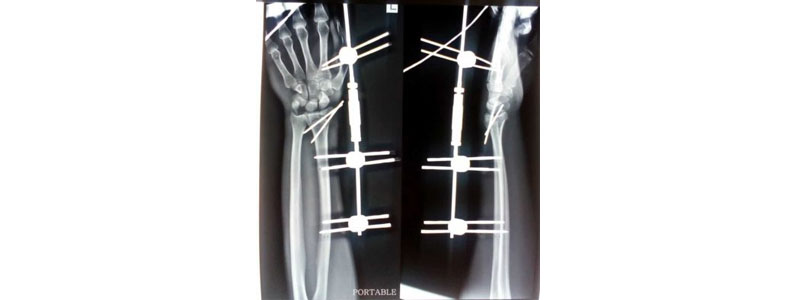

Trauma surgery specialty deals with operative and non operative / conservative management for traumatic injuries to bones, muscles, tendon and nerve. Depending upon type and nature of fracture (displaced / non-displaced) treatment can vary from plaster / cast / splint to open reduction and fixation with plate and screw or intramedullary nailing and repair of tendon, muscle and nerve. Line of management also depend upon patient age and co morbidities.